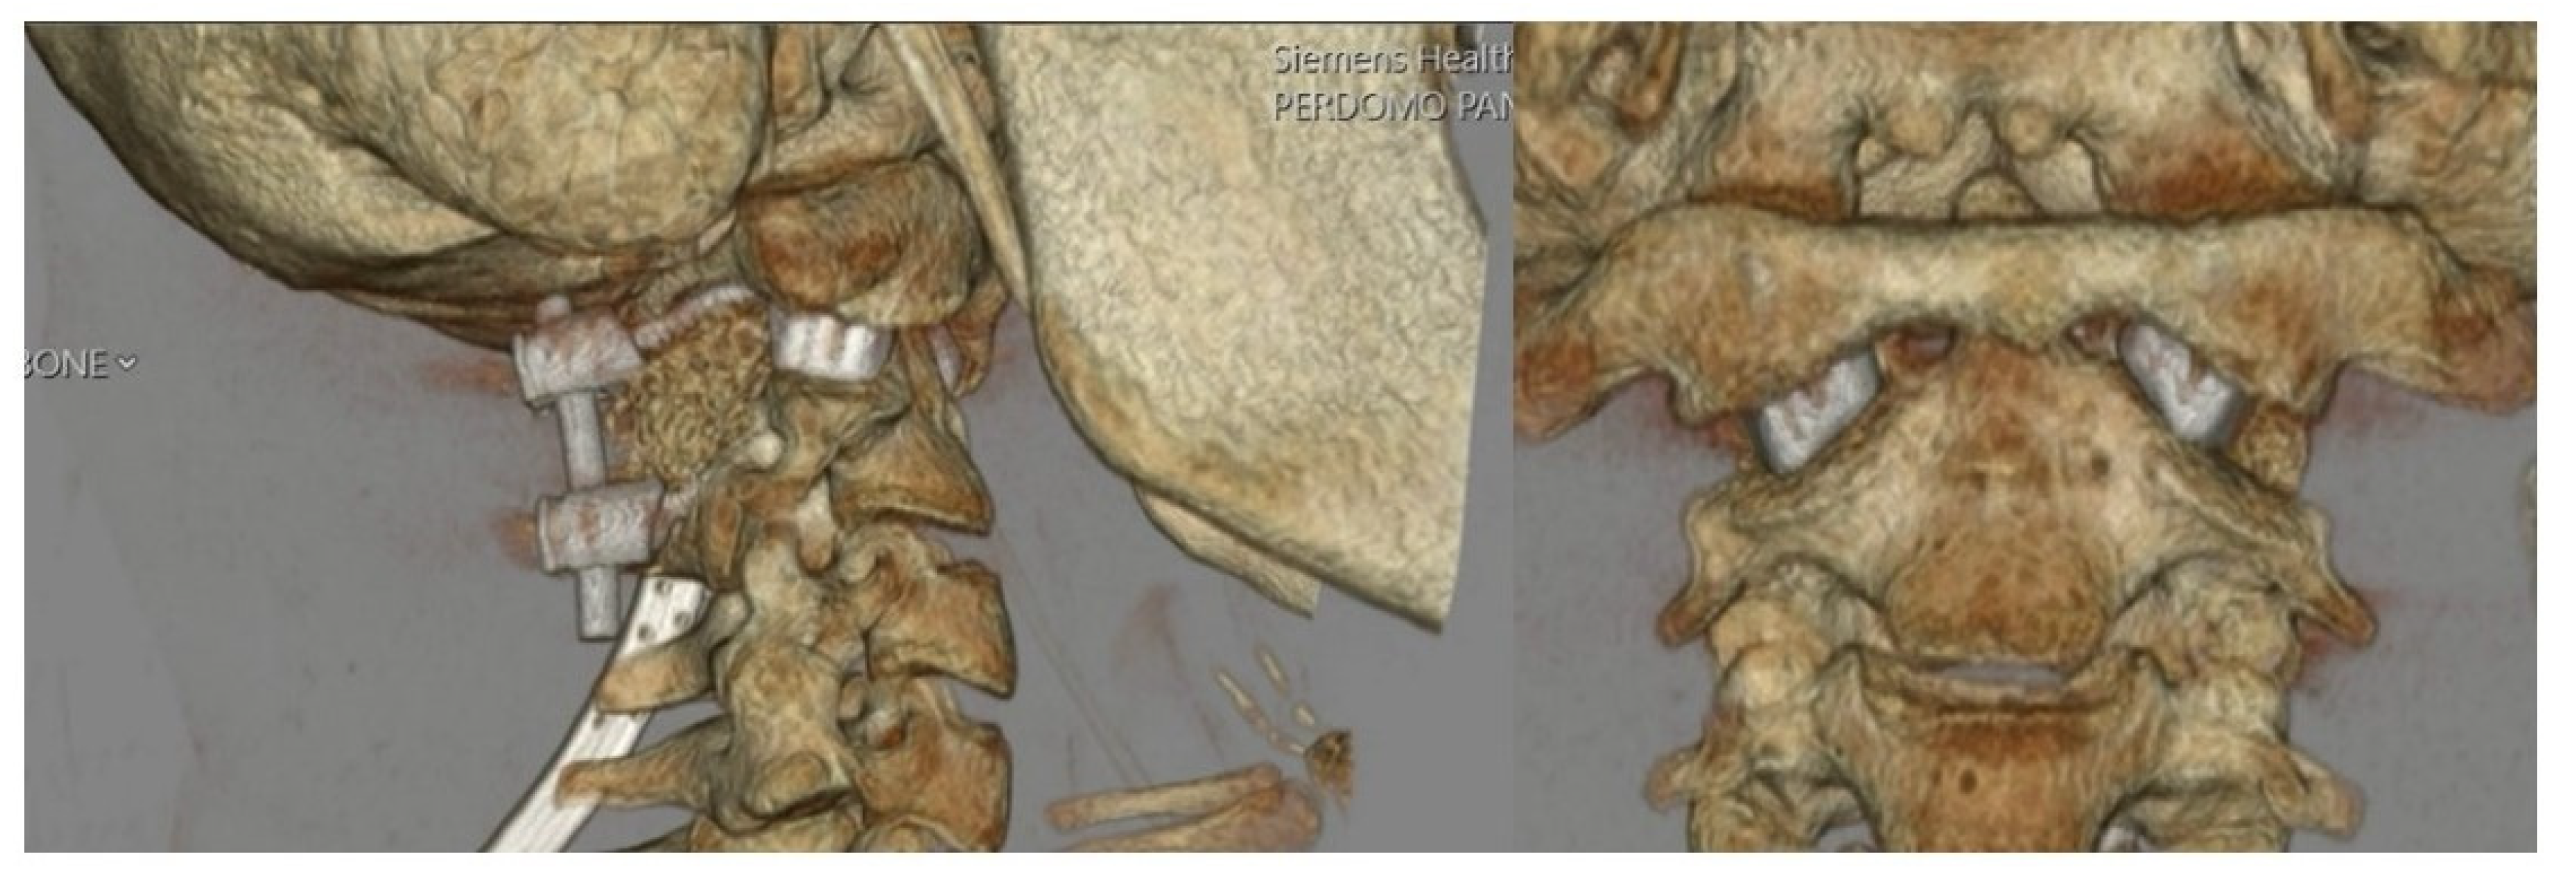

2.2. Imaging and Diagnosis

3.1. Preoperative Planning and 3DPI Design

4. Results